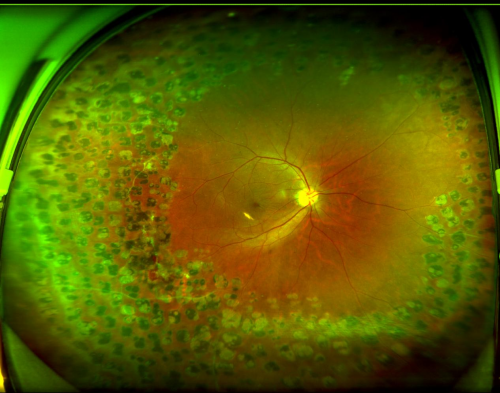

图:张先生右眼眼底 2026年1月20日,赵铁英院长为张先生顺利实施了“右眼微创玻璃体视网膜病变手术+黄斑前膜、内界膜剥离术+气体填充术”。 术后恢复期间,张先生右眼的视物变形逐渐消失。2月24日复查时,视力已提升至0.8,视觉质量明显改善。